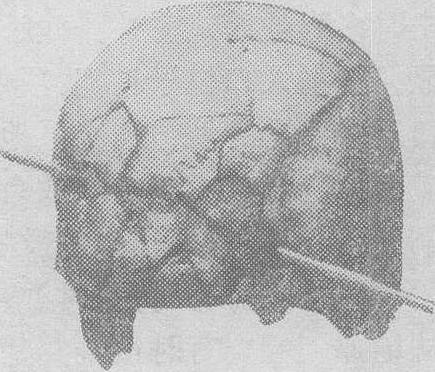

骨上的弹创管呈截头圆锥形,圆锥体的尖端指向弹头飞来的方向(图6)。如弹头垂直击中骨质,则弹创孔呈圆形,其直径与弹头直径一致或稍小(因骨质有一定弹性)。弹创孔周围常有放射状及同心圆性骨折线,故颅骨枪弹创常致粉碎骨折(图7)。头部二次枪弹创所致二个创孔周围的放射状骨折线相交时,后形成的骨折线常止于先形成的骨折线。脑贯通性枪弹创所致脑实质损伤亦呈圆锥形,射入口端窄,射出口端较宽。肝脏及脾脏贯通枪弹创的入口及出口均呈星芒状撕裂,但射出口大于射入口,并有组织外翻。

图7 颅骨枪创所致的粉碎性骨折(枕部与射入口)